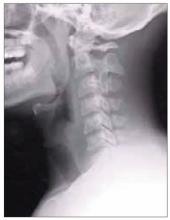

Figure 4. The patient’s magnetic resonance image. Top, an axial T2 image with contrast; bottom, sagittal T1 image with contrast. The white matter lesions indicate she is at risk of developing multiple sclerosis.

Our patient undergoes MRI, which shows lesions on axial T2 and sagittal T1 imaging with contrast (Figure 4). Of note, there are significant lesions perpendicular to the corpus callosum (Dawson fingers), some of which enhance with contrast. The enhancement indicates breakdown of the blood-brain barrier and suggests that there is active inflammation in the white matter.